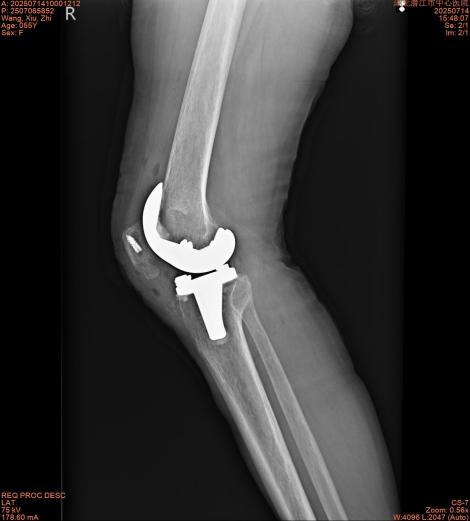

手術(shù)過程非常順利,在骨外科Ⅱ醫(yī)生團隊精湛的技術(shù)操作下,成功將王女士受損的膝關(guān)節(jié)置換為合適的人工關(guān)節(jié)假體。術(shù)后,護理團隊立即介入,為其量身定制了個性化康復(fù)方案。在醫(yī)護人員指導(dǎo)下,王女士術(shù)后當天即開始了踝泵運動和股四頭肌收縮練習,第二天則進行了屈膝、直腿抬高等功能訓(xùn)練。令人欣喜的是,術(shù)后第三天,王女士已能在助行器的輔助下下床行走,這一進展讓王女士及其家人驚喜不已。

此次王女士的快速康復(fù)經(jīng)歷,生動展現(xiàn)了潛江市中心醫(yī)院骨外科Ⅱ在全膝關(guān)節(jié)置換術(shù)(TKA)領(lǐng)域精湛的技術(shù)實力與成熟的快速康復(fù)(ERAS)理念。該科室相關(guān)負責人表示,接下來將持續(xù)引進先進技術(shù)和設(shè)備,不斷優(yōu)化手術(shù)流程和ERAS方案,致力于為更多關(guān)節(jié)疾病患者保駕護航,重燃生活“膝”望!(潛江市中心醫(yī)院,通訊員:徐秀慧、董紀榕)